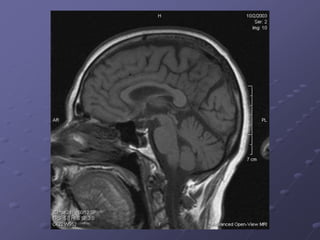

Central Nervous System

CNS

Brain

Subdivisions of Brain

1. Brain Stem

a. Midbrain

b. Pons

c. Medulla oblongata

2. Cerebellum

3. Diencephalon

Thalamus and

Hypothalamus

4. Cerebral Hemispheres